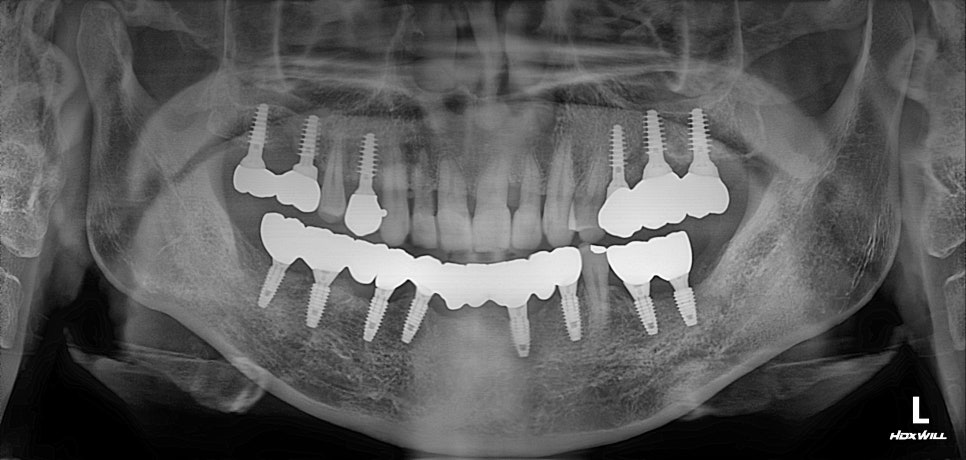

앞니 교정 + 윗쪽 임플란트

이때 "최소침습임플란트" 로

무절개로 시술하였으며

최소침습임플란트를 사용할 경우

뼈상태가 좋지 않을 때

초기고정력을 얻기 유리한 경우가 많습니다.

치료가 완료된 상태입니다.

아래쪽은 전반적으로 뼈상태가 좋지 않아서

위에 비해 치료시간이 오래 걸리긴 했지만

UV임플란트와 PDRN을 이용하여

최대한 치료기간을 단축하였습니다.